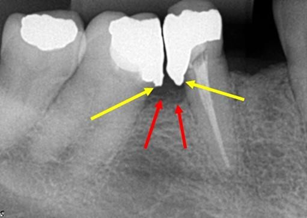

Figure 3Interproximal radiography of the molars and premolars D region, diagnosed on panoramic radiography. The arrows point to the distal of tooth 45, showing excess of amalgam restoration, in the distal box, which characterize iatrogeny. Note that the alveolar bone crest is already in the process of resorption.

Figure 4 Periapical radiography of the molars and lower premolars region D. There is a fixed prosthesis with three elements, teeth 45 and 47 being pillars. Suspended element 46. Note the lack of material in the distal of tooth 45 and the excess in the mesial of the tooth 47, which characterize iatrogeny. Both teeth are treated endodontically. The endodontic treatment of teeth 44 and 45 is correct, apparently.